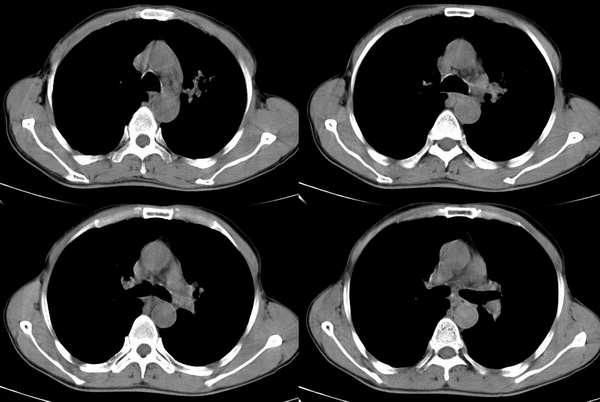

男,58岁,咳嗽1月加重1周,伴痰中带血

临床表现结合ct定位像看更支持肺结核,慢性机化肺炎也要考虑,高年龄更要注意肺癌存在.

首先考虑肺结核.结核好发部位,下面几幅图像不是很支持肿块.

左上肺病灶与胸膜脂肪线存在,未见明显胸膜凹陷征,虽然病灶边缘不规则,但未见明显“短毛剌、切迹征、免耳征、血管束集征”,其间亦见条索状、斑点状影,认为左上肺结核或炎性病变>周围型肺癌。